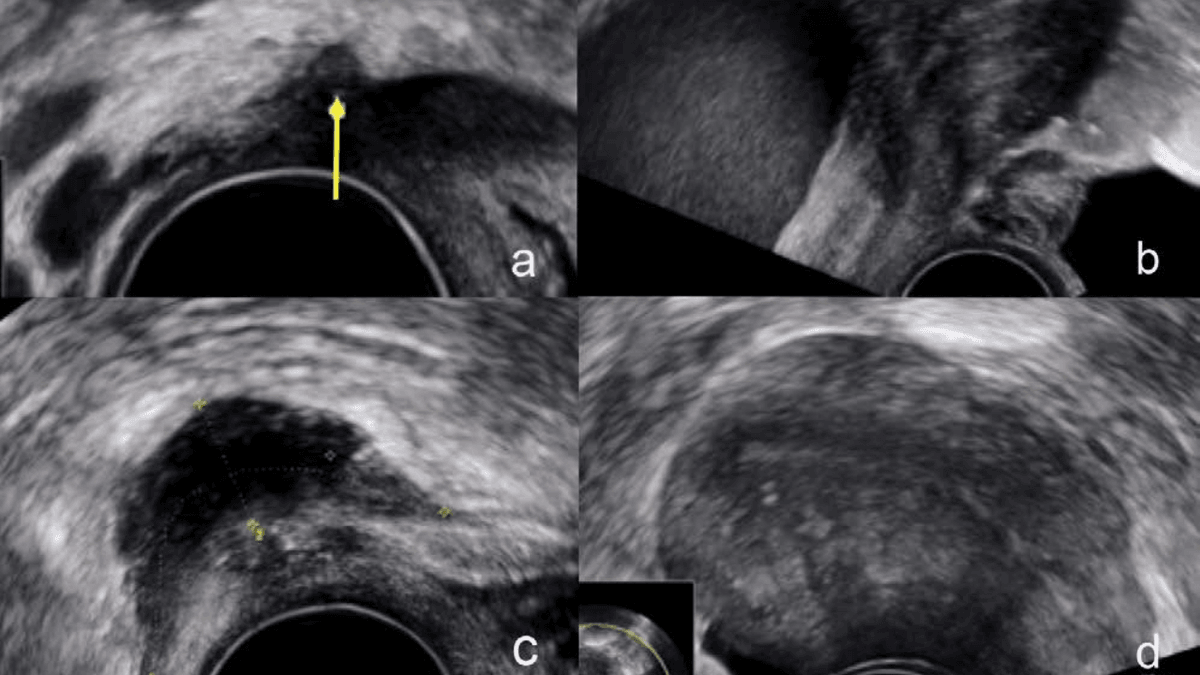

Verschiedene Erscheinungsformen der Endometriose lassen sich auch in der mikroskopischen Untersuchung des Gewebes erkennen.